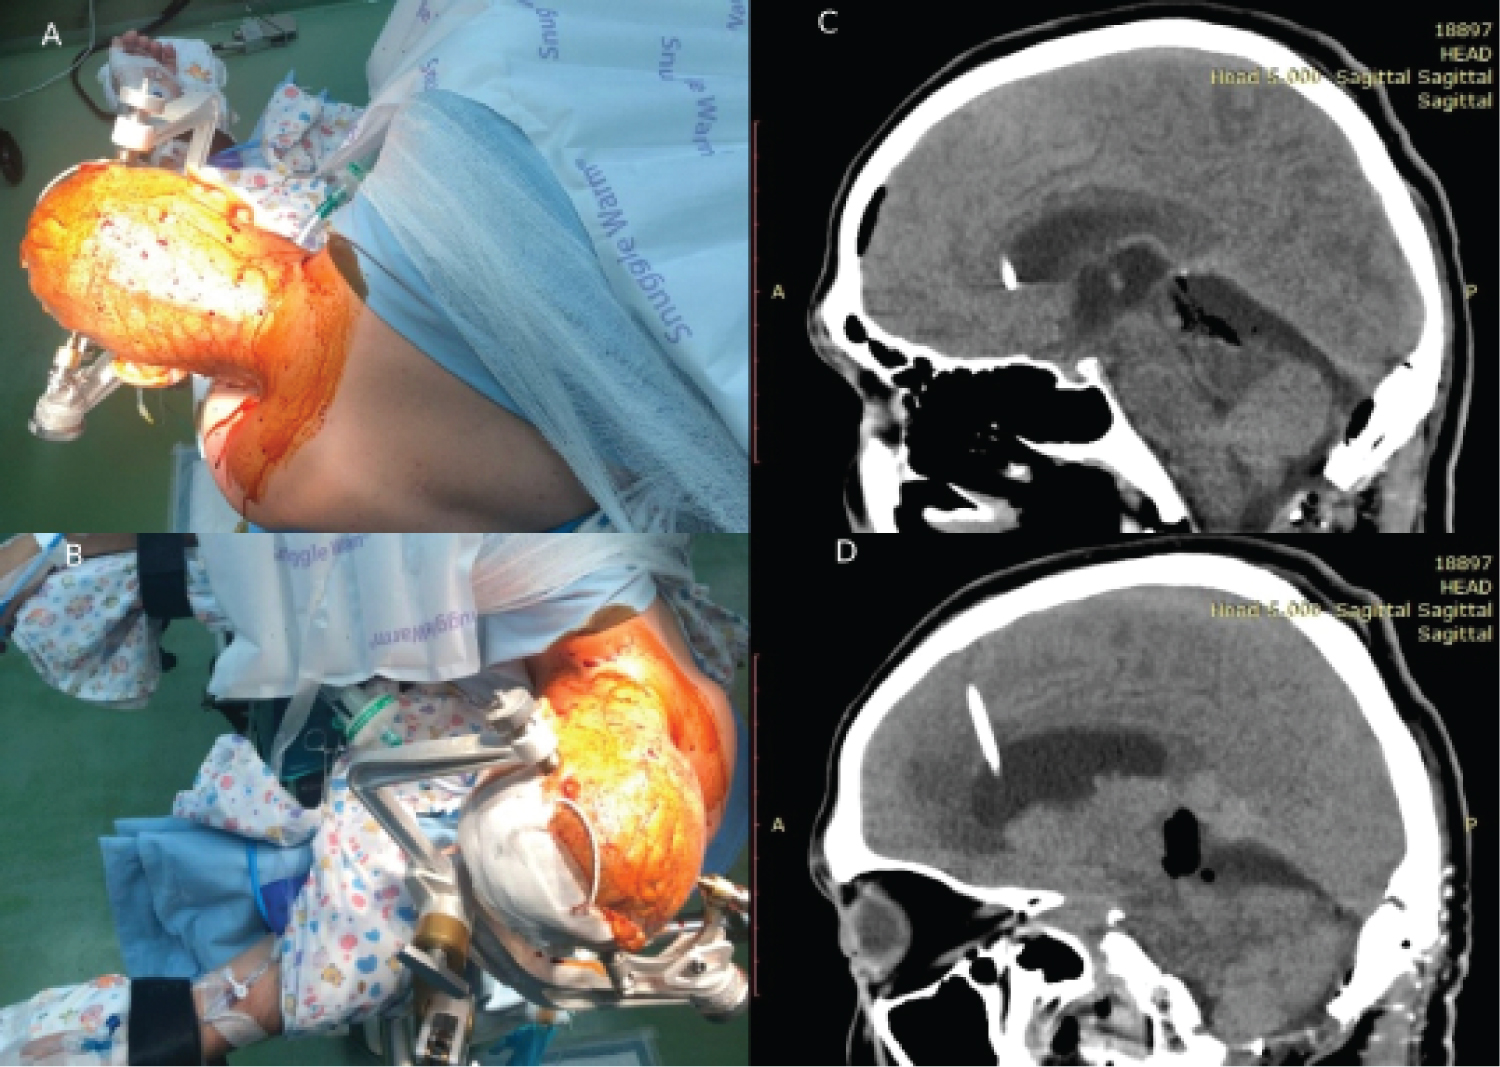

The decision was made to perform a midline supracerebellar infratentorial approach with the patient in a modified park-bench position (Figure 2A and Figure 2B). We prefer not to use a sitting position, instead, we place the patient in a modified park-bench position so the traction will help to open the quadrigeminal cistern. Two burr holes were made over the transverse sinus, afterward, a craniotome was used to connect the burr holes, and the bone flap was elevated. Dura was incised in a curvilinear fashion and opened to the top. The tenting sutures over the tentorium were placed to expand the operative corridor. After the tentorium was released, the operative corridor was gone through incisures, where the tumor was founded. It is important that the midline vermian bridging vein was saved, which is seen in the video. External detachment of the tumor was performed with the combination of the suction tube and bipolar forceps to safely unplug the tumor from vascular structures. En bloc complete tumor removal with the capsule was achieved. The final steps were aimed at complete hemostasis with bipolar coagulation. The postoperative field was draped by Surgicel to provide hemostasis. Total blood loss was approximately 300 ml. The pericranial autograft was used for a watertight dural closure. The patient was observed in the intensive care unit for 1 day and the postoperative course included steroids, mannitol, and furosemide once daily. He also received one liter of isotonic NaCl solution for three days to prevent any electrolyte complications.

Figure 2: A,B) Patient position and the incision line are shown; C,D) Sagittal CT scans after gross total resection. The operative route is seen. No signs of complications. View Figure 2

CT-control after the operation is shown in Figure 2C and Figure 2D. After the operation patient's hearing loss is completely resolved. The external ventricular drainage was removed three days later. He was discharged home on day eight after the second operation.